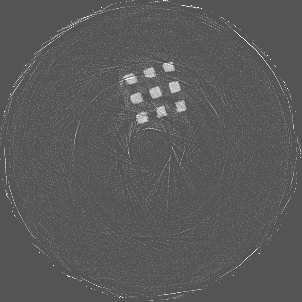

Figure 7 shows a single slice spectral reconstruction of the Mg scaffold. Due to low atomic number of Mg (Z = 12) compared to Ti (Z = 22), the results did not exhibit any significant beam hardening effects. Low energy reconstruction shows good spatial information while high energy ranges are limited by photon noise. In scans involving smaller samples made from low-Z materials like Al or Mg, acquiring low energy quanta in CSM provide high spatial information with minimum or no beam hardening effects. Figure 8 illustrates a single slice spectral reconstruction of the Ti mesh. Similar to the Ti scaffold, streaks are less pronounced in the mid and high energy ranges.

Beam hardening and metal artefacts pose challenges during CT imaging in the presence of metal hardware [17]. This paper presents data that demonstrates the use of spectral imaging in reducing beam hardening effects and metal artefacts. A high-Z sensor layer like CdTe is necessary to provide improved spectral resolution at higher x-ray energies needed for typical implant visualisation. Multi-energy acquisition of metal samples has the added advantage of capturing spectral information which exhibits reduced artefacts and reasonable non-metal (tissue) information. Further, the results were obtained without any hardware filters (except for the intrinsic filter-equivalent in the x-ray tube) and without any numerical corrections. A global reduction in noise due to charge sharing effects was seen due to the availability of CSM. 3D visualisation of the samples (figure 9) revealed finer spatial structures.